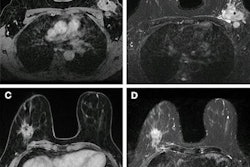

From left to right: axial T2-weighted images, axial T1-weighted images before contrast agent administration, real subtraction images (first postcontrast subtracted images), virtual low–signal-to-noise ratio (SNR) images, synthetic images generated with approach A, and synthetic images generated with approach B. Images in a 62-year-old woman (patient A) with invasive breast cancer that was stage pT1c, NST grade III, and triple-negative. Contrast enhancement (blue arrows) was accurately reconstructed by both approaches. Images in a 57-year-old woman (patient B) with invasive breast cancer that was stage pT1c, NST grade II, and luminal B. Approach B missed the contrast-enhancing lesion (red arrow). Images in a 64-year-old woman (patient C) who presented for follow-up after resection of invasive breast cancer 1 year prior. Contrast enhancement is both missed (red arrow, fibroadenoma) and falsely synthesized due to scar tissue (yellow arrow) by approach B. Images in a 44-year-old woman (patient D) who presented for screening. No contrast-enhancing lesions were seen. However, approach B synthesized contrast enhancement (yellow arrow). Images and caption courtesy of the RSNA.Müller-Franzes and colleagues found that the radiologists could not distinguish the synthetic images from the real post-contrast-enhanced images. Radiologist 1 was correct in choosing 49 of 100 images while radiologist 2 chose 55 out of 100 images correctly. The study also showed that, when using images generated according to approach B, the two radiologist readers correctly determined whether an image was real or synthetic for 67 of 100 images (p < 0.001) and 55 of 100 (p = 0.18).